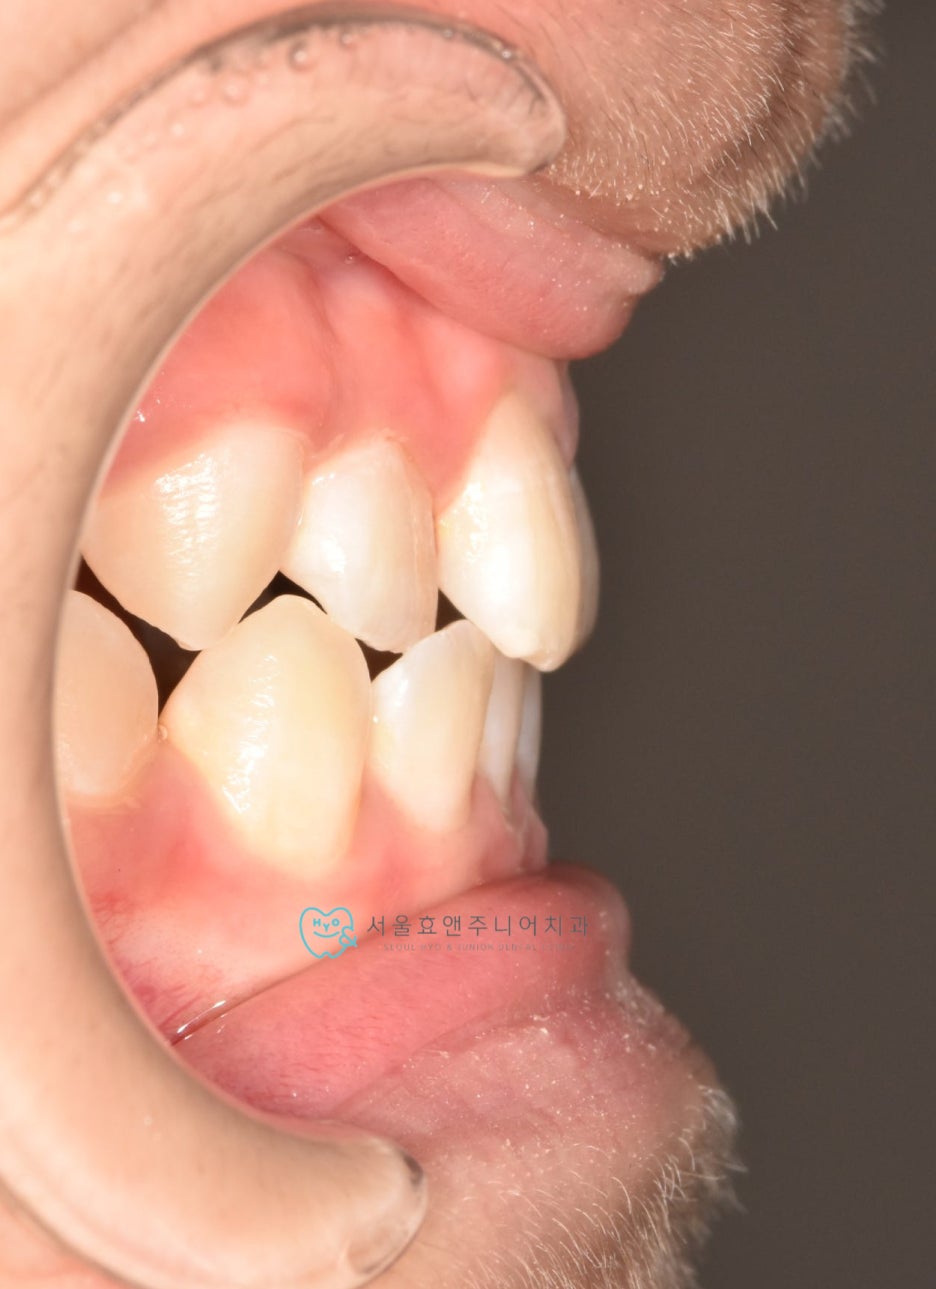

초진사진입니다

초진사진입니다. 11세 5개월 환아로, 반대교합을 보이고 있습니다. 반대교합으로 인해 치아가 부딪혀 치은퇴축(잇몸이 내려감)도 보이고 있네요.(화살표)